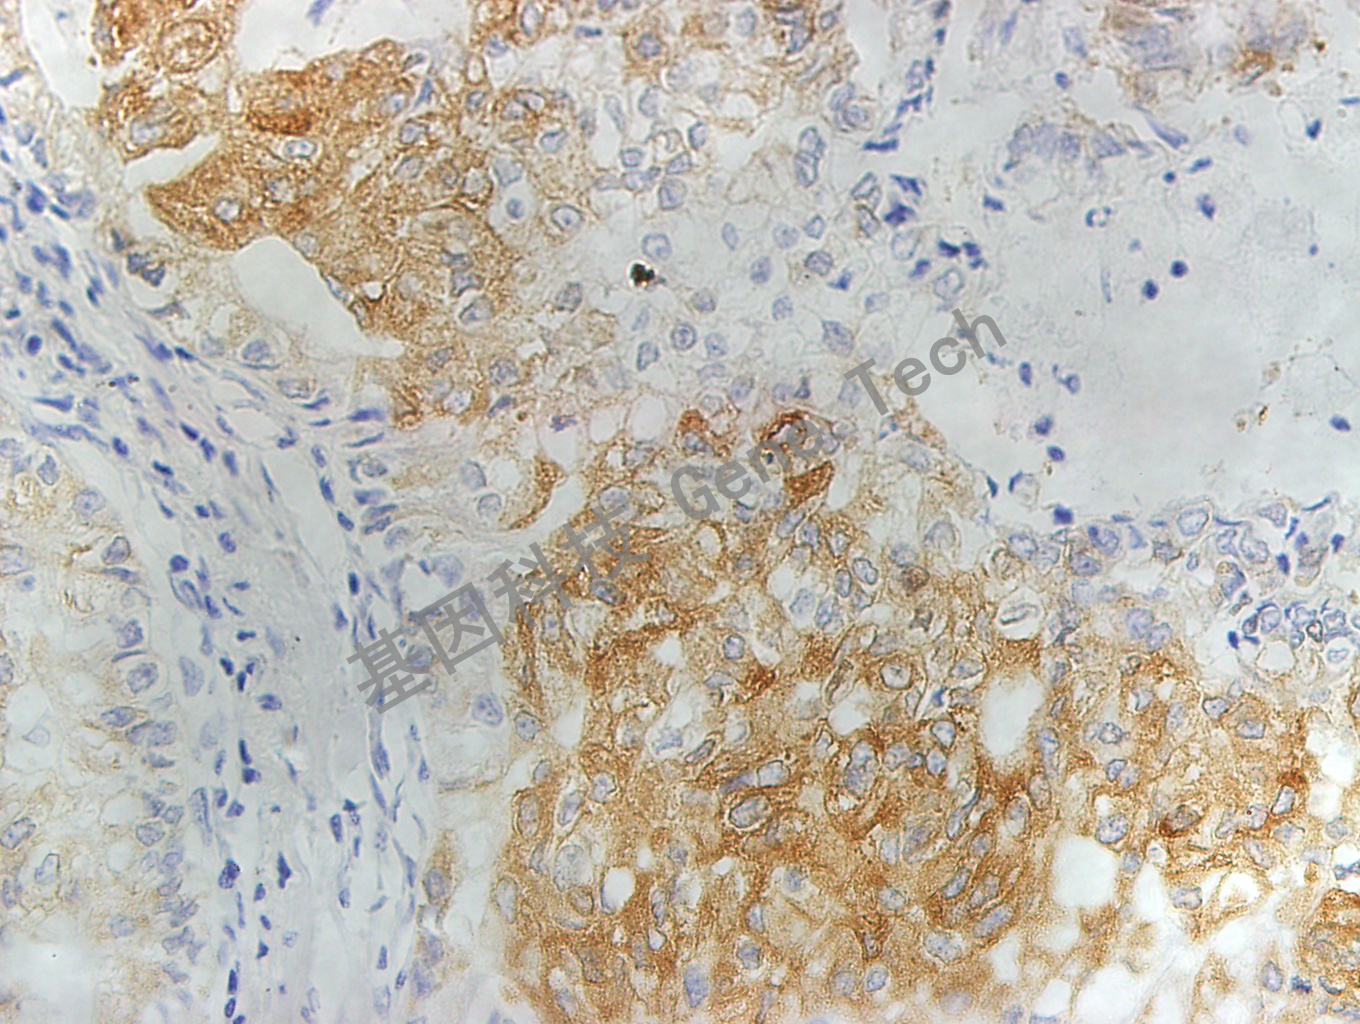

| 預(yù)處理:高pH熱修復(fù) | 陽性部位:細(xì)胞漿 | 陽性對照:乳腺癌 |

| 肺石蠟切片,用 MRP1(GT2015)染色,細(xì)胞漿陽性,DAB 顯色 | ||